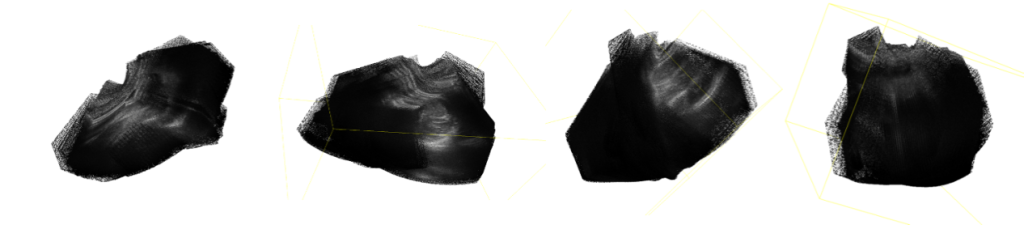

团队的初始目标是还原出手臂的三维模型。他们从一个大型医学影像比赛的数据集中获取了手臂的超声影像数据,但这些数据里除了骨骼,还有大量软组织、血管等信息混杂在一起,很难清晰地分离出有效的特征点进行处理。

(手臂超声图像的初始点云)

面对这种情况,团队决定暂时放下复杂的人体数据,改为用更容易处理的日常物品进行实验。“因为这次项目的主要目的是验证算法的可行性,让我们这些本科生趁暑假体验一次完整的科研过程。”张皓南说道。

他们选择了轮廓更清晰的的背包、行李箱等物品,取得了出色的成果。从对比图中可以看出,原本稀疏、不规则的初始点云,经过算法7000次、30000次的迭代优化后,变得愈发密集和规整,最终渲染出的三维图像与真实物体高度接近。